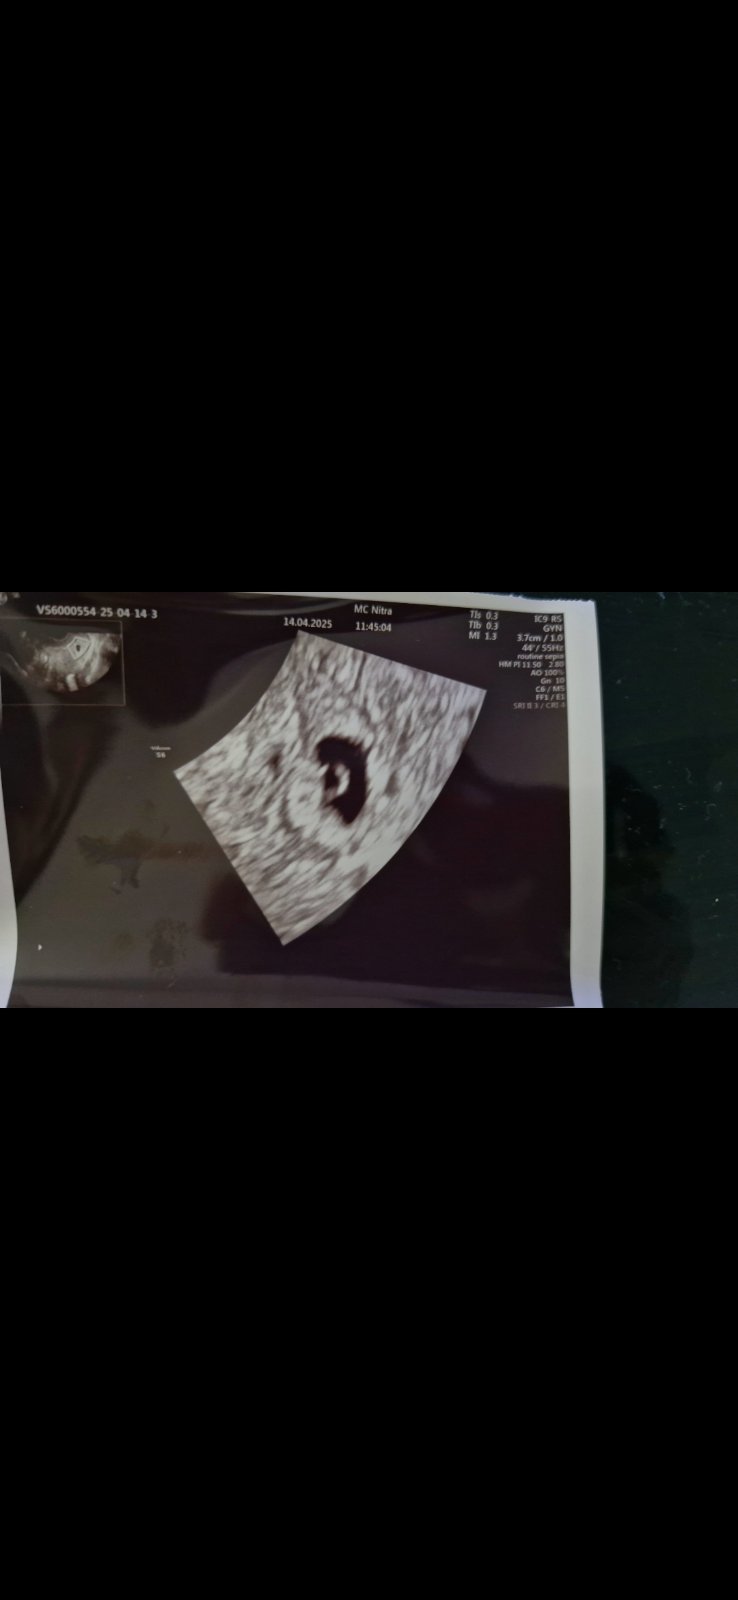

Ja len sa chcem opýtať či už niečo bude vidno na Sone dnes ma Gynekologička objednala na pondelok 14.4

Určite bude vidieť či je to v maternici alebo nie. čiže môže vidieť plodovy vak, či bude vidno už aj plod neviem

No lekári vychádzajú z tej poslednej menštruácie, takze 14.4 by si už mala byt tusim prebiehajúci 7tt a to uz by bola vidno aj akcia srdiečka, tak preto ta asi objednala..lebo asi sa ta pýtala len na termín poslednej menštruácie..ak chces mat pokoj na dusi a neísť tam potom o týždeň-dva znova a týždeň cakat či sa tam objaví, aj cinnost, tak sa preobjednaj o týždeň, ale zas, ak ti nie je problém ísť potom znova, tak kľudne chod, povedz lekárke všetky tieto detaily a ona ta usmerni..plodový vak by tak či tak malo byt vidno, pripadne ti vezmu krv

Cize dajme tomu ze ovulaciu si mala 21.3. a 14.4. uz chces nieco vidiet na usg? Mozno nieco vidiet bude, ale priprav sa aj na moznost, ze tam budu len prvotne zmeny.